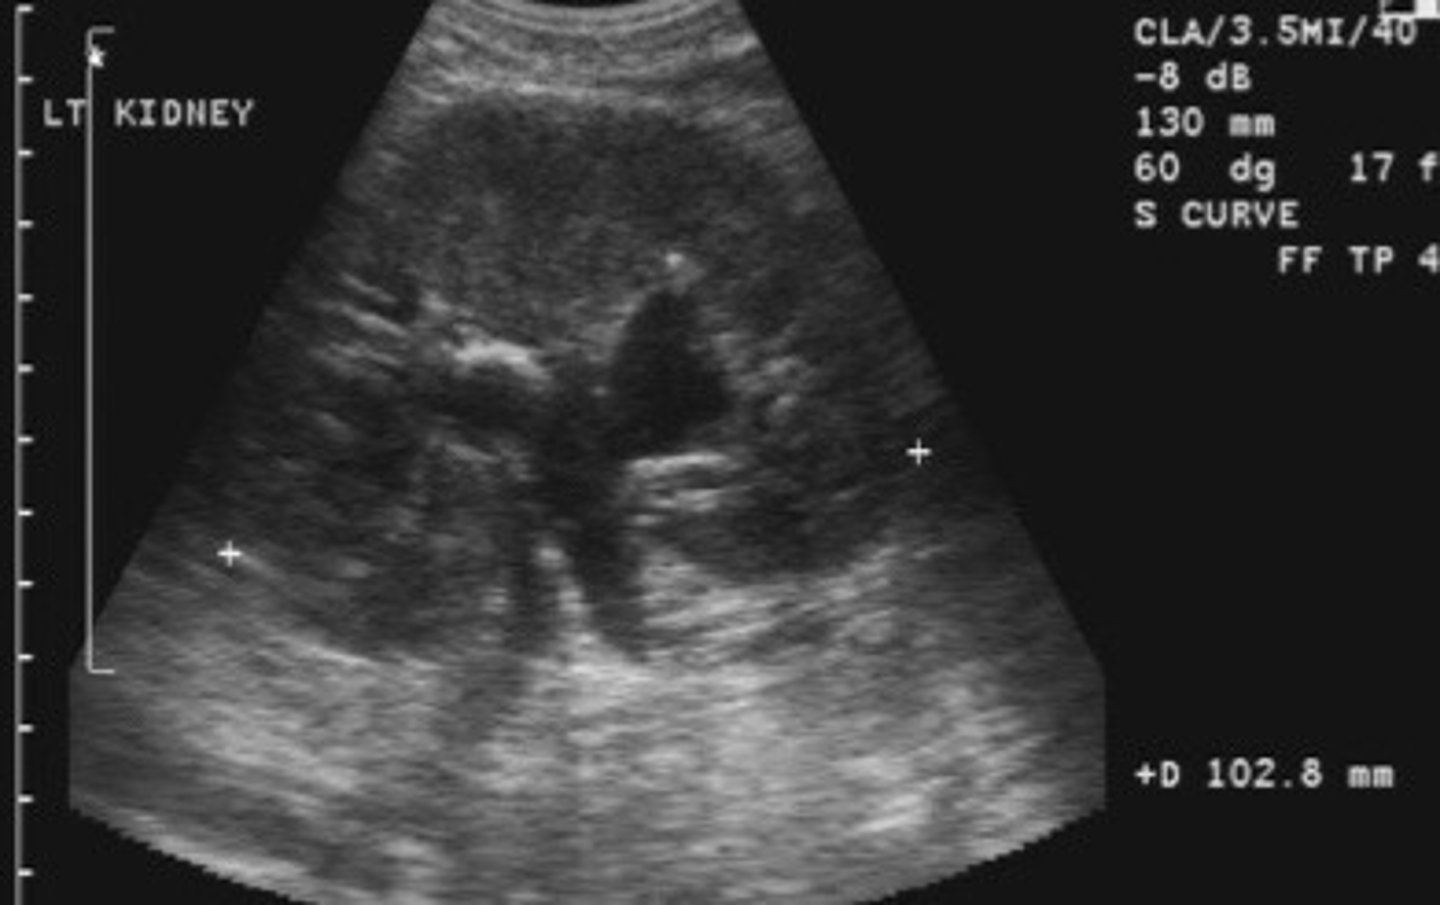

Grade 2 hydro

What does this image show

<p>What does this image show</p>